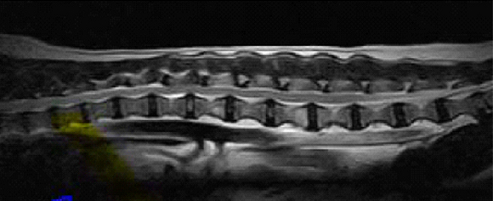

【画像診断】~ダックスフンド、雄10歳、グレート3の椎間板ヘルニア~

▲MRIのT2強調の矢状断面(キャミックに依頼)